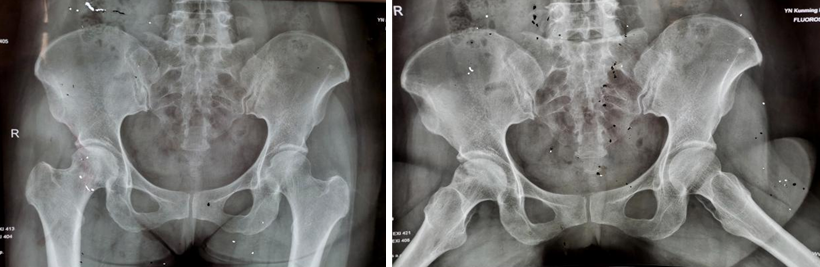

两年多前,34岁的王先生因双髋部疼痛伴活动受限4月余,在家人的搀扶下,一脸痛苦地来到昆明医科大学第二附属医院骨科就诊。杨振东副主任医师接诊了这位患者,该患者饮酒史10年,每日2两,戒酒1月,右髋外旋活动受限,左髋活动正常,右髋“4”字试验阳性,结合影像学资料显示,该患者右侧股骨头凹凸不平、黯淡无光,且有部分塌陷,诊断为右侧股骨头坏死。

入院3天后,杨振东医师为该患者进行了吻合血管的游离腓骨移植手术治疗。患者全麻生效后取右侧仰卧体位,杨振东医师先从患者身上取长约8CM带血管蒂骨,然后进行股骨头病灶彻底清除,最后截取合适长度游离腓骨,植入股骨颈内,吻合游离雕骨血管至旋股外侧动静脉。手术持续约6小时,手术顺利,患者复苏后安返病房。

术后12个月和24个月,患者来院复查,影像片子显示患者右侧股骨头髋臼平整光滑,股骨头圆润光滑,股骨头内骨小梁密度均匀,已恢复至正常股骨头状态,几乎与正常人股骨头无异。患者随访时说:“来医院之前,我独立行走都困难,短短几米的距离,我可能要花费三四分钟才能走完。手术之后,我不仅可以健步如飞,还能做下蹲等动作,也不必担心重体力劳动导致股骨头无法承受的问题,这个手术真的是太好了,不仅救了我,也救了我一家人……”